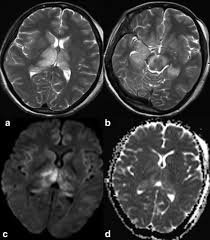

Diffusion Imaging In Brain Infections Radiology Key

Diffusion Imaging In Brain Infections Radiology Key from radiologykey.com

Two subtypes are recognized which differ in demographics, virus, and pattern of involvement. Become a gold supporter and see no ads. Bilateral temporal lobe t2 hyperintensity refers to hyperintense signal involving the temporal lobes on t2 weighted and flair imaging. Hypertrophic pachymeningitis is a condition where there is localized inflammatory thickening of the dura. Limbic encephalitis, mca ischaemia, tumours, effects of seizures) hyperintense t2 signal in the medial temporal lobes, inferior frontal lobes and insula basal ganglia are usually spared Reference osborn a, et al. Given the history of fever and seizures coupled with the mri findings of bilateral mesial temporal lobe changes, herpes encephalitis requires clinical consideration. The changes spare the basal ganglia, a feature which is helpful in distinguishing an mca infarct with hemorrhagic transformation from herpes simplex encephalitis, the diagnosis in this case. Mri demonstrates extensive edema in the right temporal lobe with areas of intrinsic high t1 signal, in keeping with hemorrhage. It is estimated to occur in ~2% of pati. The differential diagnoses include limbic encephalitis (paraneoplastic), gliomatosis cerebri, and status epilepticus. It is reasonable to obtain an mri when patients are asymptomatic to ensure that no other abnormality is present which may be causing a recurrent chemical meningitis (e.g. Axial t2 prominent swelling, increase t2 signal involving the left temporal lobe and insular cortex.

Axial t2 prominent swelling, increase t2 signal involving the left temporal lobe and insular cortex. Two subtypes are recognised which differ in demographics, virus, and pattern of involvement. Multilocularis.the larval stage is the cause of hydatid disease in humans 1. Cerebral malaria is a rare intracranial complication of a malarial infection. The changes spare the basal ganglia, a feature which is helpful in distinguishing an mca infarct with hemorrhagic transformation from herpes simplex encephalitis, the diagnosis in this case.

Axial t2 prominent swelling, increase t2 signal involving the left temporal lobe and insular cortex. It is estimated to occur in ~2% of pati. Become a gold supporter and see no ads. This patient went on to have hsv encephalitis proven on csf pcr. A brain biopsy was performed and the histology was consistent with encephalitis. The differential diagnoses include limbic encephalitis (paraneoplastic), gliomatosis cerebri, and status epilepticus. Multilocularis.the larval stage is the cause of hydatid disease in humans 1. It is usually bilateral but asymmetrical. Spinal hydatid disease is an uncommon manifestation of hydatid disease, caused by the larval stage of echinococcus granulosus, or less commonly e. Limbic encephalitis, mca ischaemia, tumours, effects of seizures) hyperintense t2 signal in the medial temporal lobes, inferior frontal lobes and insula basal ganglia are usually spared It is reasonable to obtain an mri when patients are asymptomatic to ensure that no other abnormality is present which may be causing a recurrent chemical meningitis (e.g. 10 public playlist includes this case Pcr was repeated on the biopsy specimen and was positive for hsv.